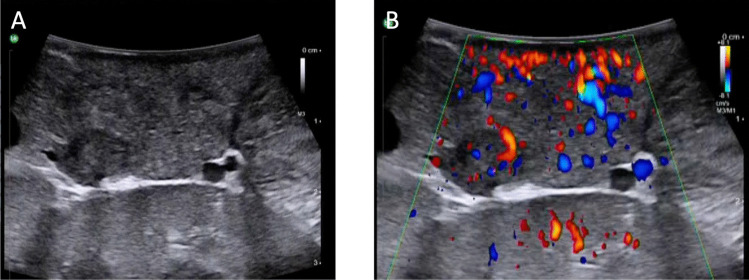

A disadvantage of robotic surgery is the lack of haptic feedback making intraoperative tumour localisation by palpation not conductible, thus requiring precise preoperative imaging. Intraoperative ultrasound and tumour visualization tools are promising strategies to compensate for this drawback, if an NET cannot be visualized in preoperative cross-sectional imaging [36, 37] (Fig. 1). Novel approaches to facilitate intraoperative GEP-NETs localisation are outlined in detail below.

Fig. 1.

Intraoperative ultrasound (A) and colour-coded duplex sonography (B) during robotic resection of a well-differentiated insulinoma (arrows) in the pancreatic tail